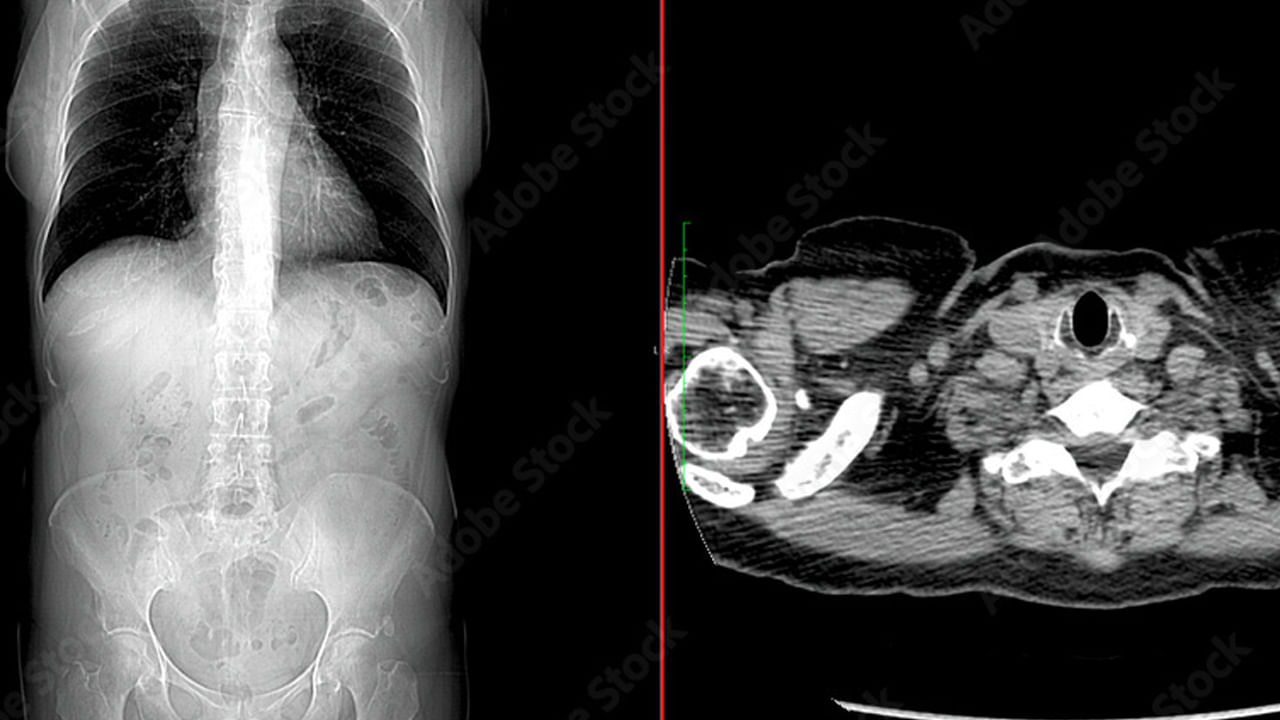

ఉత్తరప్రదేశ్ రాష్ట్రంలోని కౌశాంబి జిల్లాకు చెందిన 21 ఏళ్ల యువతి ఓ అరుదైన మానసిక రోగం కారణంగా ప్రాణాలు కోల్పోయే ప్రమాదంలో చిక్కుకుంది. చిన్ననాటి నుంచే జుట్టు తినే అలవాటు పెంచుకున్న ఆమె కడుపులో 1.5 అడుగుల పొడవైన భారీ జుట్టు బంతి ఏర్పడింది. వికారమైన అలవాటు కారణంగా ఆ జుట్టు కడుపులో పేరుకుపోయి ‘ట్రికోబీజోర్’ అనే పరిస్థితికి దారితీసింది. దాంతో యువతికి కడుపునొప్పి, వాంతులు, బలహీనత, ఆకలి లేకపోవడం మొదలయ్యాయి. అయితే, ఆమె పలుచోట్ల స్కాన్లు, పరీక్షలు చేయించుకున్నా.. అసలు కారణం ఏంటనేది ఎవరూ గుర్తించలేకపోయారు. ఇటీవల ఆమెను ప్రయాగ్రాజ్లోని నారాయణ స్వరూప్ ఆసుపత్రికి తీసుకువచ్చారు. అక్కడ డాక్టర్లు పూర్తి చెకప్ చేసిన తర్వాత కడుపులో హెయిర్ బాల్ ఉన్న విషయం గుర్తించి.. వెంటనే శస్త్రచికిత్స చేయాలని నిర్ణయించారు.

డాక్టర్ రాజీవ్ సింగ్, డాక్టర్ విషాల్ కేవలాని, డాక్టర్ యోగేంద్ర, డాక్టర్ రాజ్ మౌర్యల బృందం కలిసి రెండు గంటలపాటు శస్త్రచికిత్స జరిపారు. కడుపు ఓపెన్ చేయగా 1.5 అడుగుల పొడవు, 10 సెం.మీ వెడల్పు, సుమారు 500 గ్రాముల బరువు ఉన్న హెయిర్ బాల్ కనిపించింది. దాన్ని జాగ్రత్తగా తీసి, పేగులన్నీ శుభ్రం చేసి, దెబ్బతిన్న భాగాలకు చికిత్స చేశారు.